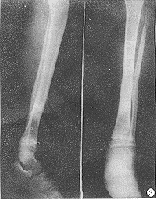

愈合的时间:骨愈合时间确定较难,首先是标准问题。多数人认为:骨小梁穿过骨折端加上病人能完全持重而不需要任何支持,又不伴有疼痛。闭合性无移位骨折的骨愈合需要10-13周;移位的骨折13--16周;而开放性或粉碎性骨折则需16-26周。平均愈合时间,成年人为16周。迟缓愈合和不愈合也很难单纯以时间来划分。但是,要诊断骨折不愈合,临床上骨折端必须有假关节活动,x线检查骨折端必有硬化,骨髓腔封闭,骨端萎缩或肥大。这时再等待已无用,必须采取进一步治疗措施。

骨折线的方向与愈合时间无明显关系,但斜型或螺旋型骨折常常系间接暴力致伤,局部软组织损伤的程度较轻,而直接暴力常造成横断骨折或粉碎骨折,软组织损伤较重可能会影响愈合时间。当然,造成多段骨折的暴力更重,软组织损伤也更严重,骨愈合常常要超过6个月。

关于骨折的部位与愈合时间的关系,多数人认为中下1/3交界处胫骨的血运较差,故愈合时间较长。但是,经过若干作者统计学研究,胫骨中下1/3交界处骨折的愈合时间与其他部位无明显差别。胫骨骨折时腓骨是否骨折对愈后的影响:腓骨完整本身说明致伤的暴力较小。因此,软组织损伤也较轻。又由于腓骨的支撑,胫骨就较稳定,移位相对较轻。但是,腓骨的支撑也使胫骨不易完全复位,特别易造成向外成角。同时骨折端的接触也差,反而延迟胫骨的愈合,当确定有胫骨迟延愈合或不愈合时,打断腓骨以增加胫骨的接触,以促使胫骨愈合,也是一种可行的办法。